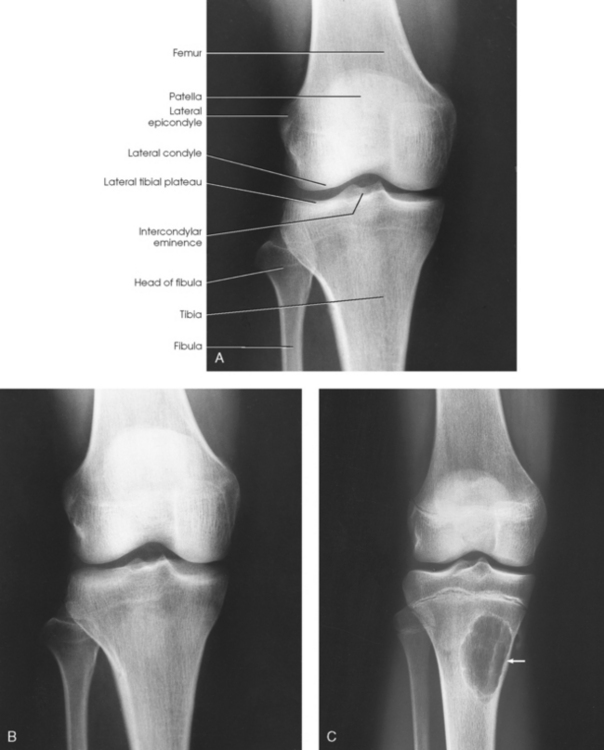

Structures shown: The resulting image shows an AP projection of the knee structures (Fig. 6-121).

Structures shown: The resulting image shows the joint spaces of the knees. Varus and valgus deformities can also be evaluated with this procedure (Fig. 6-128).

Structures shown: The PA weight-bearing method is useful for evaluating joint space narrowing and showing articular cartilage disease (Fig. 6-130). The image is similar to images obtained when radiographing the intercondylar fossa.

Structures shown: The resulting image shows an AP oblique projection of the laterally rotated femoral condyles, patella, tibial condyles, and head of the fibula (Fig. 6-132).

Structures shown: The resulting image shows an AP oblique projection of the medially rotated femoral condyles, patella, tibial condyles, proximal tibiofibular joint, and head of the fibula (Fig. 6-134).